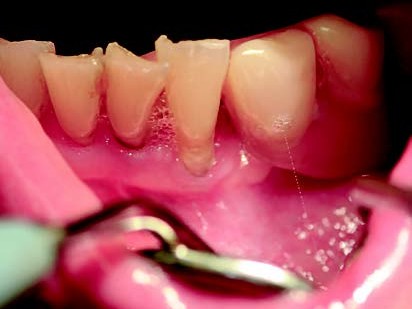

Eine 72-jährige Patientin stellte sich mit einer teleskopierenden Arbeit vor, die seit über zehn Jahren bestand. Der Teleskop-Pfeilerzahn 33 (Abb. 1) war nach Wurzelkanalbehandlung (Abb.2) aufgrund einer rezidivierenden apikalen Ostitis entfernt worden (Abb. 3). Hauszahnärztlich war ein Heil- und Kostenplan mit dem Ziel erstellt worden, sämtliche Unterkieferzähne teleskopierend zu versorgen. Dieser Vorschlag war der Patientin zu invasiv und überstieg vor allem ihre wirtschaftlichen Möglichkeiten als Rentnerin. Der Vorschlag, die bestehende Teleskoparbeit unter Insertion eines Implantates in regio 33 mit der Versorgung über das industriell gefertigte SynCone-Konuskronenprinzip zu erhalten, erschien der Patientin als eine einfache, gute und auch wirtschaftlich für sie realisierbare Alternative sinnvoll. Daraufhin wurde in regio 033 im Rahmen der Spätimplantation ein ANKYLOS C/X-A-Implantat (Durchmesser 3,5 und Länge 14 mm) inseriert (Abb. 4). Nach einer Einheilungsphase von zwei Monaten erfolgte die Implantatfreilegung. Bei der Implantatinsertion zeigte das Implantat einen Osstell-Messwert von 76 ISQ, bei Implantatfreilegung einen ISQ-Messwert von 82. Nach Überprüfung der Parallelität kam ein ANKYLOS SynCone C/ Aufbau 5° der Gingivahöhe 4,5 zur Anwendung. Dieser wurde mit 15 Ncm Drehmoment angezogen. Chairside wurde mit Unterstützung durch den Zahntechnikermeister vor Ort die ANKYLOS Degulor-Konuskappe SynCone 5° mit Retentionen eingearbeitet. Es erfolgten Nachkontrollen halbjährig. Bei der Zweijahres-Nachschau berichtete die Patientin unaufgefordert, dass sie mit der Rettung ihrer schon über zehn Jahren bestehenden Teleskoparbeit die richtige Entscheidung getroffen hatte und dass diese noch bestens in Funktion sei, wie diese selbst demonstrierte (Abb. 5-7).